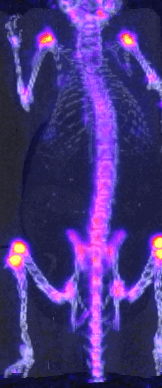

Tomographie par émission de positons (TEP)

Modèle: Imaging research and Technology IR&T, LabPet

Description: Technique d'imagerie médicale permettant d'obtenir une image 3D de la présence d'isotope (décroissance Beta)

Caractéristique: Résolution sous-mm ; corps entier de la souris ; mesures statiques et dynamiques